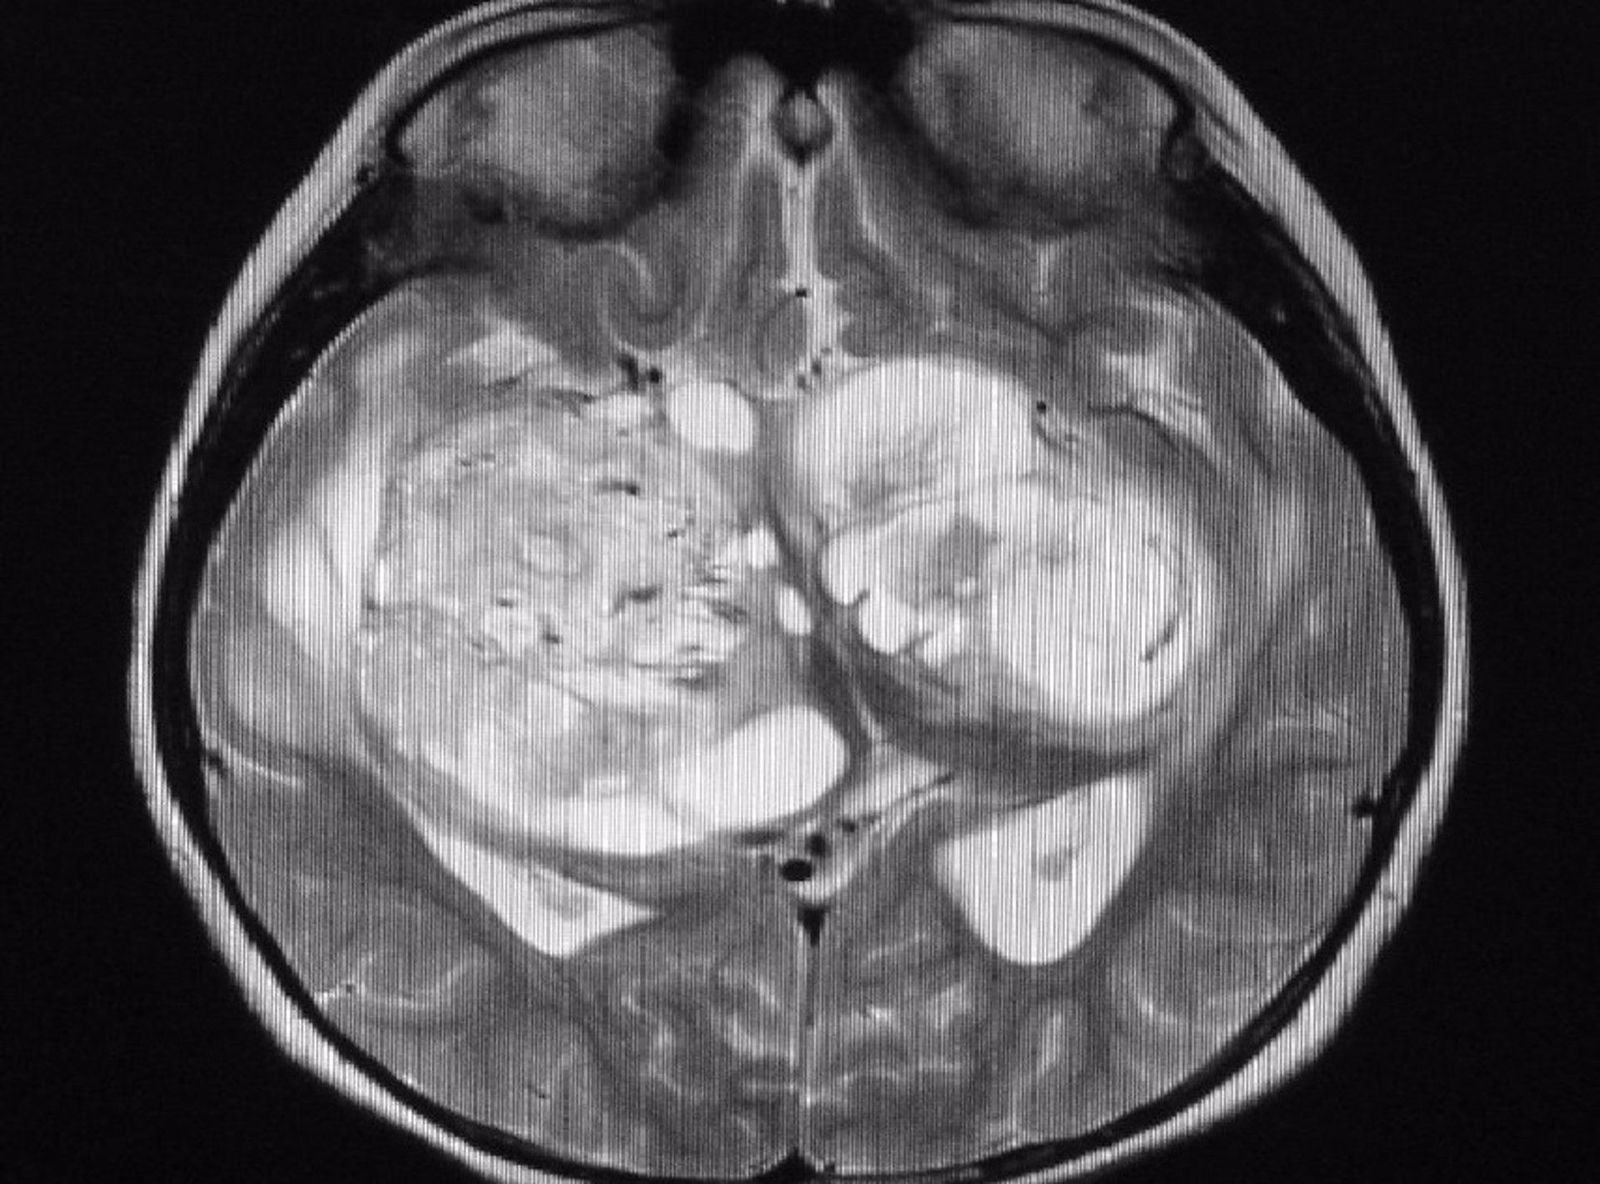

Un estudio internacional codirigido por la Universidad de California (UCLA) ha descubierto que el fármaco vorasidenib duplica con creces la supervivencia libre de progresión en personas con glioma recurrente de grado 2 con mutaciones IDH1 e IDH2, un tipo de tumor cerebral mortal, retrasando el momento de empezar con quimioterapia o radioterapia.

En comparación con las personas que recibieron un placebo, las que tomaron vorasidenib pasaron casi 17 meses más sin que su cáncer empeorara. El hallazgo sugiere una posible nueva opción de tratamiento para las personas con este tipo de tumor cerebral de crecimiento lento pero mortal.

El glioma recurrente de grado 2 con mutaciones IDH1 e IDH2, tiende a afectar a las personas más jóvenes, a menudo a los 30 años. El tratamiento estándar actual, una combinación de radiación y quimioterapia, puede causar déficits neurológicos que dificultan que los pacientes aprendan, recuerden cosas nuevas, se concentren o tomen decisiones cotidianas, todo lo cual puede ser especialmente desafiante para las personas que tienen familias jóvenes.

El estudio ha involucrado a 331 personas de 12 años o más que habían sido diagnosticadas con glioma de grado 2 recurrente con las mutaciones IDH1 e IDH2 y que se habían sometido a una cirugía de tumor cerebral. De ese grupo, 168 fueron asignados al azar para recibir vorasidenib y 163 recibieron placebos.

Entre los que recibieron vorasidenib, la enfermedad no progresó durante un promedio de 27,7 meses, mucho más que los 11,1 meses de los que recibieron el placebo. Y entre los que recibieron vorasidenib, el 85,6 por ciento pasó 18 meses antes de su próximo tratamiento, mientras que el 83,4 por ciento pasó 24 meses entre tratamientos.

La enfermedad progresó en solo el 28 por ciento de las personas que recibieron vorasidenib, en comparación con el 54 por ciento de las que recibieron placebos. Y en septiembre de 2022, 30 meses después de que comenzara el estudio, el 72 por ciento de los pacientes que estaban en el grupo de vorasidenib seguían tomando el medicamento y su enfermedad no había progresado.